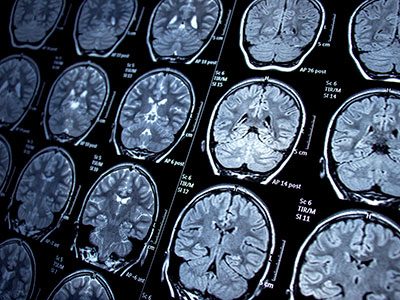

His innovative research utilizes advanced structural and functional imaging to examine the effects of epilepsy on brain structure and function. His pioneering work with functional imaging has changed clinical practice for patients with epilepsy, made important technical contributions to structural and functional imaging methods, and provided fundamental scientific insights on the biology of brain plasticity. Ultimately, the goal of his research is to improve the outcomes and lives of children with epilepsy.